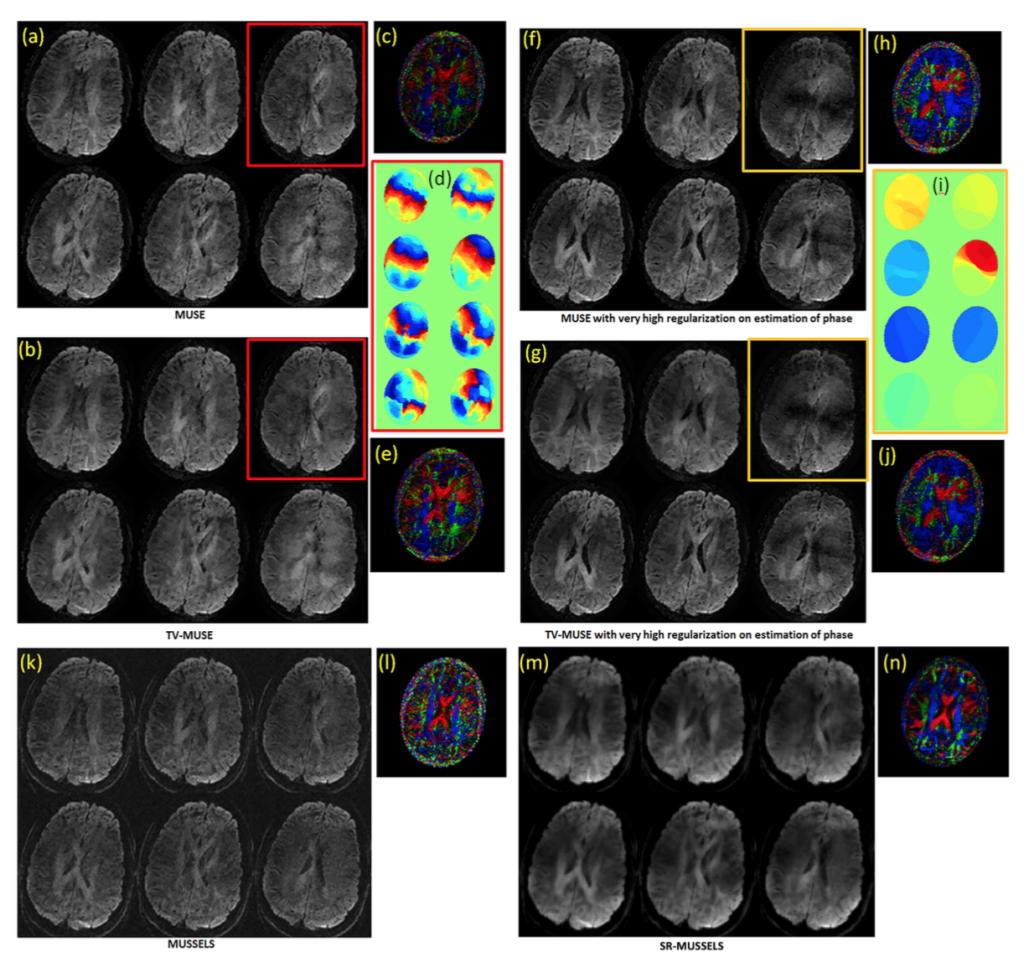

The recovery of 8-shot diffusion data can be challenging due to the fewer number of sampled data points present in each shot. Because of the absence of a fully sampled center k-space, the phase estimates obtained from the shots can be noisy. Hence the reconstructions that depend on the phase estimates may not achieve good unaliasing in such situations. MUSSELS with no additional constraint will generate noisy results since it is hard to characterize the k-space filter corresponding to the phases from the smaller number of samples present in the compact filter. However the reconstruction can be stabilized by adding extra constraints. By using the smoothness regularized reconstruction provided in Eq [14], we show that we can significantly improve the unaliasing for under-sampled acquisitions as well as for data collected with a high number of shots. Figure 7 shows the reconstruction of the 8-shot MS-DWI data using unregularized and regularized methods. To introduce a similar smoothness regularizer into the MUSE framework, a total-variation based regularization was added to the MUSE reconstruction as well. The estimates of phase used in MUSE reconstruction for one of the images (indicated by the colored boxes) are also provided in the figure. The top row shows the reconstruction using MUSE with no TV during the image reconstruction. The left figure used low regularization for phase estimation (the regularization parameter was chosen to give the best reconstruction for the boxed image in 7(a)) while the right figure used higher regularization for phase estimation. The corresponding phase images are given in the panel on right; it shows that the quality of the phase images control the quality of the DWI reconstruction. The second row shows the MUSE reconstruction with TV built into the iterative MUSE implementation. However, as can be appreciated from the images, the TV reconstruction also gets only as better as dictated by the noise in the phase since these reconstructions are inherently phase-based. The third row shows the MUSSELS reconstruction without TV (left) and with TV (right). As expected the images are noisy for the unregularized case. However using the smoothness regularized MUSSELS, we can recover the MS-DWI data reasonably well.

Fig 7: 8 shot fully sampled data. The six DWIs reconstructed using various methods are shown. (a) and (f) shows MUSE reconstruction with no TV during the image reconstruction. They use TV in the estimation of estimate phase. (f) used a higher regularizer than (a) during the estimation of phase. As a result, the DWIs in (f) are denoised while the unaliasing becomes imperfect. (b) and (g) shows MUSE reconstruction with TV regularization added to the image reconstruction step also with (b) using the same phase as (a) and (g) using the same phase as (f). Inclusion of TV to the image reconstruction step has improved the MUSE reconstruction slightly however, the results are dictated by the noise in the phase estimates. (k) and (m) shows the results of MUSSELS without and with SR respectively. It can be appreciated from the color coded FA maps (e) and (l) that MUSSELS without SR achieves the better quality of reconstruction than the TV-MUSE and the results can be further improved by using SR-MUSSELS.